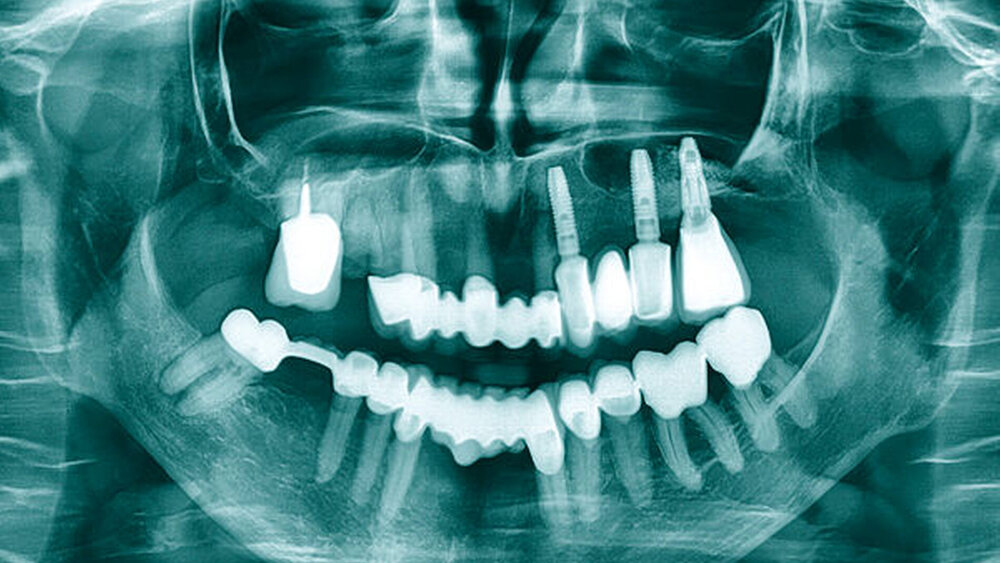

In der Panoramaschichtaufnahme (Abbildung 1) zeigte sich zusätzlich eine insuffiziente Wurzelkanalbehandlung am Zahn 16 mit einer Obliteration der nicht gefüllten buccalen Kanäle. An den Zähnen 11 und – insbesondere – 22 war ein Attachmentverlust sichtbar. Zur besseren Beurteilbarkeit der vorliegenden Knochensituation wurde eine digitale Volumentomografie angefertigt. In dieser zeigten sich horizontale Knochendefekte regio 15–22 sowie ein vertikales Knochendefizit in regio 16 (Abbildung 2).